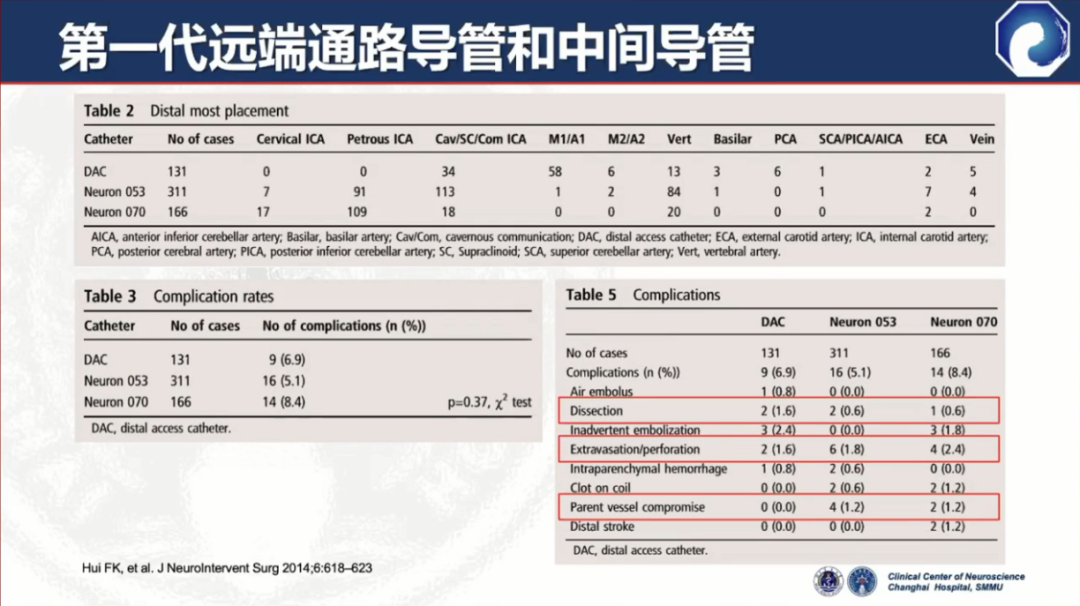

第一代远端通路导管和中间导管应运而生

代表:DAC(Stryker)、Neuron(Penumbra)

与普通导引导管相比,头端柔顺性增加,但并发症发生率仍比较高,如:夹层、血管破裂、载瘤血管闭塞等